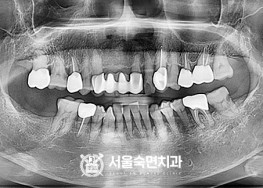

임플란트-치료-전후사진